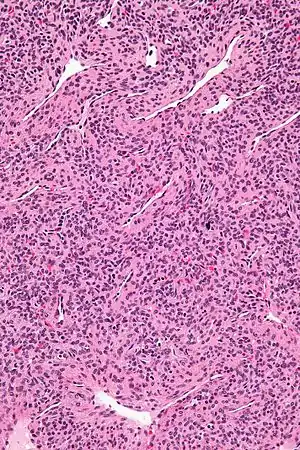

| Micrograph of a myopericytoma. H&E stain. | |